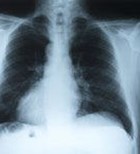

שלום, בעקבות דם בליחה מספר פעמים לאחרונה הופניתי לסיטי חזה ותרביות ליחה, רגילה ולמיקובטקריה. בסיטי חזה כתוב שהודגמה גרנמולה מסוידת זעירה בפסגת הריאה השמאלית. אך בסיכום כתוב ללא ממצא חריג. תרבית ליחה רגילה ללא ממצא פתולוגי. תרבית ליחה למיקובקטריה טרם התקבלה תשובה אך על אחת מהן כתוב כבר שלא נמצאו מתגים יציבי חומצה. מה דעתך? הגרנמולה בסיטי חזה מראה על שחפת סמויה במקרה? האם זה מחייב טיפול או מדאיג?

אציין שאני בחור צעיר יליד הארץ. בילדותי היו לי דלקות ריאה חוזרות ואסטמה. לא ידוע על חשיפה לחולה שחפת חס וחלילה.

גרנולומה זעירה

האם בעקבות זאת כדאי לבצע גם מנטו? הרופא לא נתן לי לזה הפנייה ומעולם לא עשיתי את בדיקת מנטו. תודה

שלום, גרנולומה לא מחייבת שמדובר בשחפת ישנה ויכול להיות גם דלקת ריאות ישנה אחרת. בילידי הארץ ללא סיפור עבר מתאים שיפת מאוד נדירה. אני לא חושב שאתה חייב לעשות בדיקת מנטו. נמתין לתוצאות הליחה הסופיות